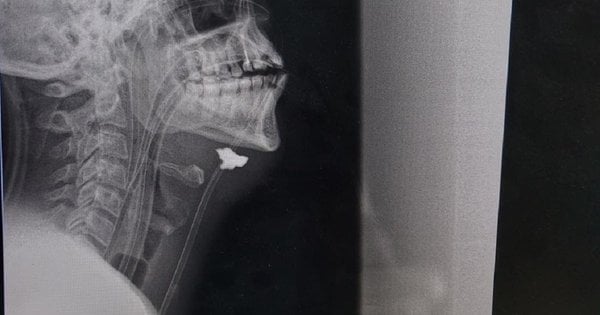

„Po vyšetreniach bola pacientovi diagnostikovaná strelná a šrapnelová slepá rana. Fragment bol nájdený v projekcii cievneho zväzku, hematómu a príznakov poranenia krčnej tepny vpravo. Inými slovami, úlomok projektilu zasiahol rameno, prešiel celým krkom, pretrhol krčnú tepnu a zastavil sa pod čeľusťou,“ povedal nám cievny chirurg Taras Kobza, ktorý dlhodobo zachraňuje vojakov na východe krajiny.

Ako vysvetlili cievni chirurgovia vo Ľvove, je veľmi ťažké zachrániť pacientov s poraneniami krčnej tepny, môžu zomrieť doslova za 5-10 minút od okamihu zranenia v dôsledku veľkej straty krvi alebo dostať mŕtvicu. Kapitán bol prijatý do nemocnice v prvej línii niekoľko hodín po zranení. Podľa chirurga ho zachránila skutočnosť, že v mieste prasknutia krčnej tepny sa vytvorili krvné zrazeniny (ochranná reakcia tela), ktoré uzavreli lúmen cievy a trochu spomalili krvácanie. Ale stratil veľa krvi.